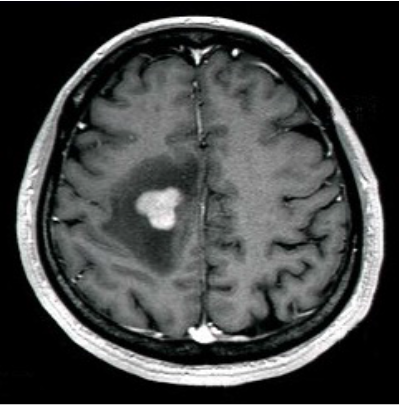

脳の造影剤を用いたMRI検査で特徴的な所見が認められることがありますが、どんな形にもなりうる腫瘍としても有名です。(左図)